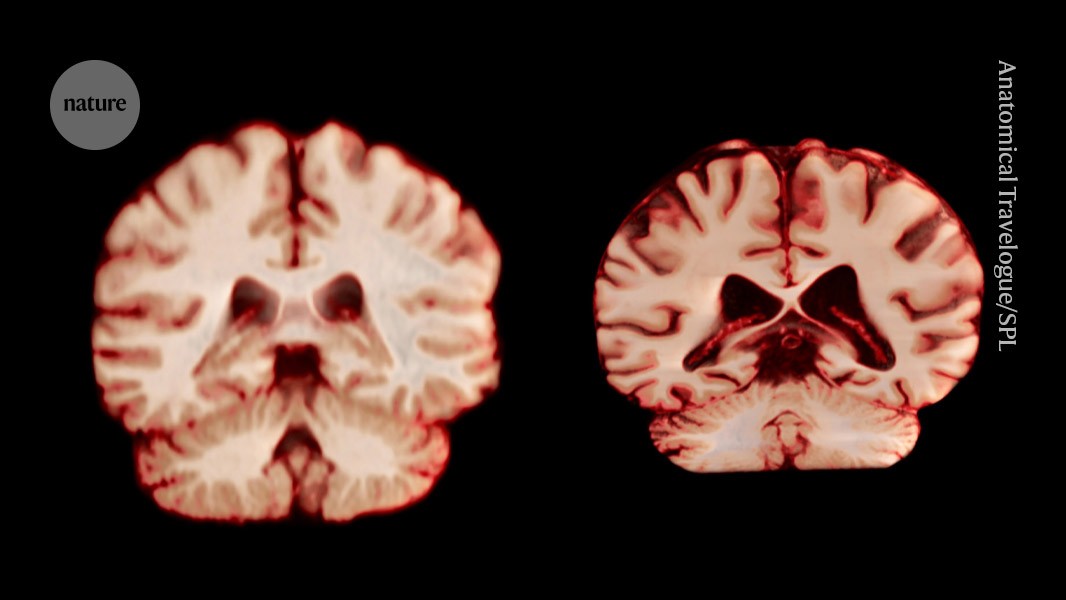

Faster Brain Shrinkage in Men and Its Link to Alzheimer’s Risk

A large MRI study found that men's brains shrink faster than women's during aging, suggesting that age-related brain volume loss does not explain why women are more frequently diagnosed with Alzheimer's disease, prompting further research into other factors like susceptibility and survival differences.